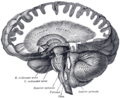

The cerebellum is located in the inferior posterior portion of the head (the hindbrain), directly dorsal to the pons, and inferior to the occipital lobe (Figs. 1 and 3). Because of its large number of tiny granule cells, the cerebellum contains more than 50% of all neurons in the brain, but it only takes up 10% of total brain volume. The cerebellum receives nearly 200 million input fibers; in contrast, the optic nerve is composed of a mere one million fibers.